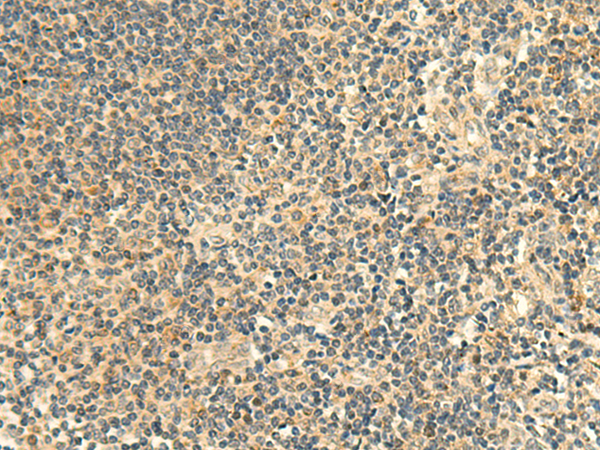

分类: 科研抗体货号: P07829别名: BDPLT15应用: WB,IHC反应种属: Human, Mouse, Rat